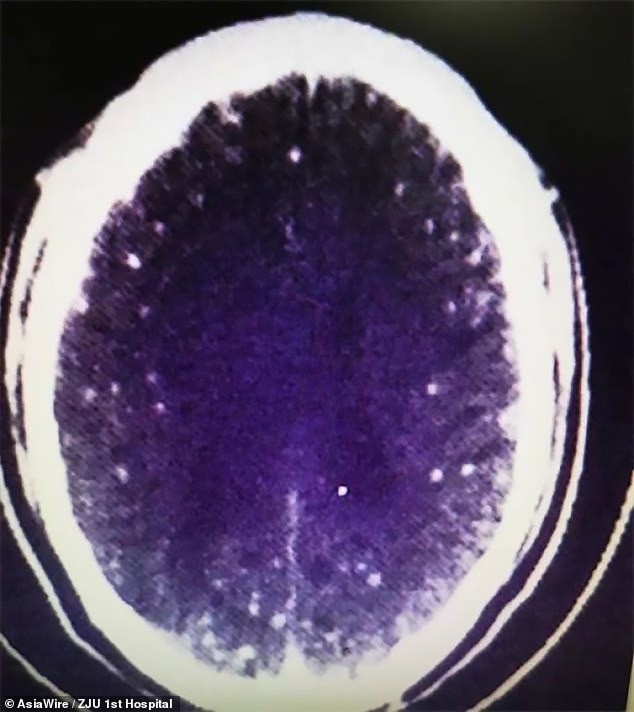

Những nang sáng trong não ông Zhu. Ảnh: Internet

Bác sĩ Huang Jianrong đến từ Bệnh viện liên kết của Trường Y khoa ĐH Chiết Giang đã yêu cầu thực hiện chụp cắt lớp MRI cho não và ngực. Kết quả hình ảnh cho thấy não và ngực ông Zhu đầy bọt giun sán lợn.

"Ông ấy không chỉ có nhiều tổn thương do não bị chiếm đóng mà còn có những nang sán trong phổi và cơ lồng ngực. Trong trường hợp này, ông ấy bị co giật và mất ý thức, nhưng có những trường hợp có nang ở phổi thì ho khan nhiều", bác sĩ Huang nói.